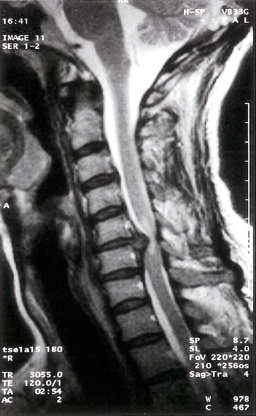

Cervical disk herniation

MRI cervical spine (T2-weighted; sagittal plane) of a patient with symptoms of cervical myelopathy A herniated disk at C5–6 effaces the dural sac and compresses the spinal cord. Hyperintense compression-induced edema is seen within the cord.